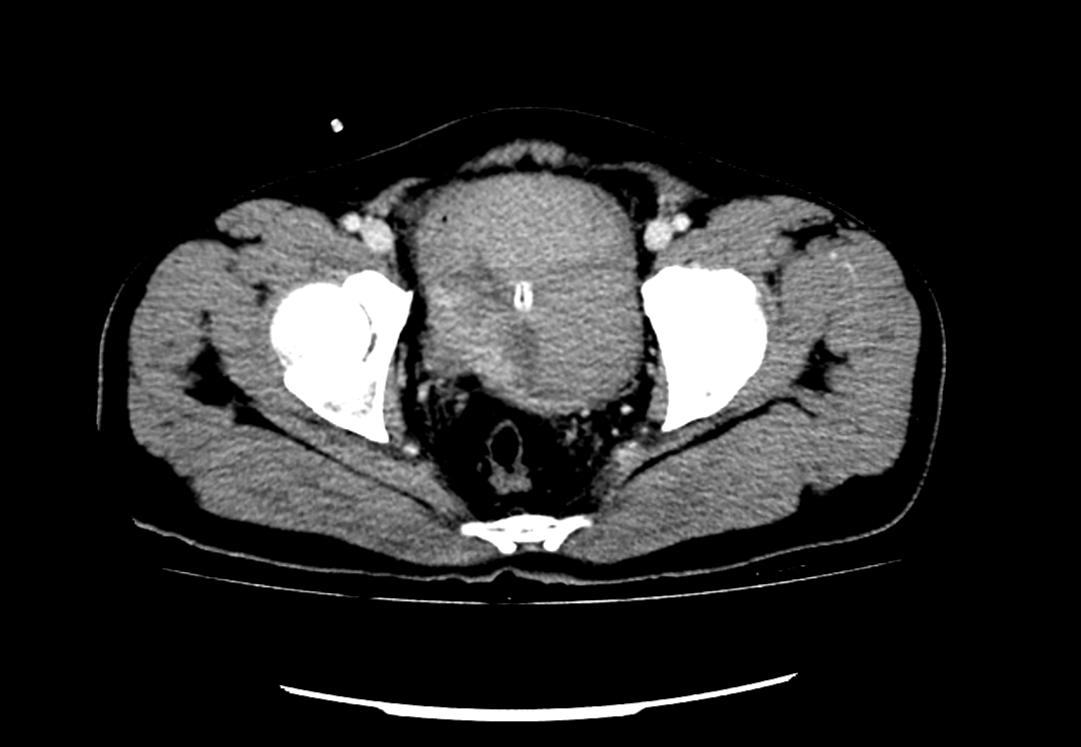

患者為53歲的男性,患者因肉眼血尿就診我院門診,行泌尿系CT考慮膀胱占位,建議患者住院治療,入院后完善膀胱MRI檢查進一步診斷膀胱腫瘤,侵犯肌層。行膀胱腫物激光切除后,病理學(xué)檢查明確“膀胱高級別尿路上皮癌,肌層浸潤”診斷,結(jié)合泌尿外科診療指南建議行根治性膀胱全切術(shù)。

泌尿外科醫(yī)生團隊術(shù)前將患者情況上報醫(yī)務(wù)科,并組織了多次會診?;颊?/span>“肌層浸潤性膀胱癌”診斷明確,術(shù)前完善心肺功能排除無明顯手術(shù)禁忌,結(jié)合指南推薦及泌尿外科團隊成員綜合意見,決定在全麻下行腹腔鏡下膀胱根治性切除+盆腔淋巴節(jié)清掃+回腸代膀胱手術(shù)。術(shù)前嚴(yán)格完善準(zhǔn)備工作,手術(shù)歷經(jīng)7小時,完整切除了患者的膀胱、前列腺及精囊,并行回腸代膀胱。手術(shù)順利,術(shù)后3天可正常行走,復(fù)查患者各項指標(biāo)正常。